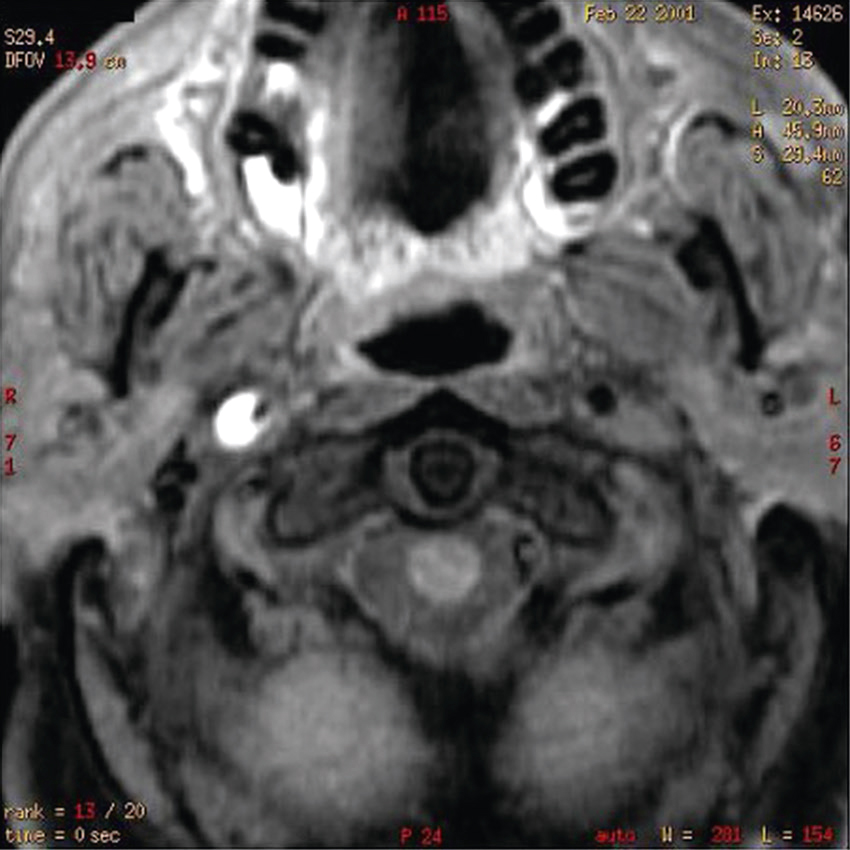

Vous faites réaliser une IRM cervicale (en séquence T2 sagittale et axiale) dont voici les résultats (fig. 31.14 et 31.15). Sur les images, que visualisez-vous ?

L'image semble être une coupe transversale obtenue par imagerie par résonance magnétique (IRM) d'une région anatomique du corps humain, probablement au niveau cervical (la région du cou). L'image montre une section horizontale vue de haut, avec des variations de densités grises correspondant aux différentes structures biologiques. Au centre de l'image, une structure ronde ou ovale de couleur foncée est visible, qui pourrait correspondre à une section de la moelle épinière ou du canal rachidien. Autour de cette zone centrale, on observe des couches de tissus avec des tonalités grises variées. Les couches musculaires paraissent bien délimitées, entourant les structures osseuses qui pourraient être les vertèbres cervicales. Ces dernières forment une structure plus claire et plus dense, de forme circulaire. L'image met aussi en évidence des zones sombres et homogènes autour des muscles, qui sont probablement des espaces remplis de fluides ou simplement des régions sans signal particulier dans cette technique d'imagerie. La qualité et les contrastes permettent de différencier les structures molles, musculaires, osseuses et nerveuses. Ce type d'imagerie est souvent utilisé pour visualiser des détails précis, comme les pathologies éventuelles des nerfs ou les anomalies structurelles dans cette région.

L'image montre une IRM de la colonne cervicale, qui est la partie supérieure de la colonne vertébrale située dans le cou. Sur cette image, on peut voir les vertèbres cervicales empilées les unes sur les autres, séparées par des disques intervertébraux. L'IRM permet de visualiser les structures internes avec une grande précision, y compris les os, les disques, la moelle épinière et les tissus mous environnants. Cette image est intéressante car elle peut révéler des anomalies telles que des hernies discales, des compressions de la moelle épinière ou d'autres pathologies qui pourraient causer des douleurs ou des dysfonctionnements neurologiques. Les vertèbres apparaissent comme des blocs rectangulaires sombres, tandis que les disques intervertébraux sont les espaces plus clairs entre eux. La moelle épinière, visible au centre, est entourée de liquide céphalo-rachidien, qui apparaît en blanc sur l'image. Cette IRM est un outil diagnostique essentiel pour les médecins afin d'évaluer l'état de la colonne cervicale et de planifier un traitement approprié si nécessaire.

-

- A compression médullaire cervicale

- B myélite cervicale

- C hernie discale C5-C6

- D syringomyélie

- E spondylodiscite cervicale